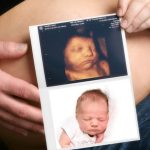

4D Ultrasound in South Delhi

4D ultrasound is a revolutionary imaging technology that allows expectant parents to witness their baby’s movements and expressions in real-time. Unlike traditional 2D and 3D ultrasounds, 4D ultrasound provides a live, moving image, offering a more immersive and emotionally enriching experience. And 4D Ultrasound Scans are not available on maximum Diagnostic Centre in South Delhi. Dr. Rupali’s Medical & Diagnostics Centre is rirst to introduce 4D Colour Ultrasound Machine- GE VOLUSON in South Delhi which gives pin-pointed diagnosis & accuracy.